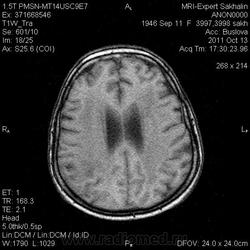

Ишемический инфаркт

ОНМК по ишемическому типу в бассейне правой СМА. Судя по очагам накопления в коре, подострое.

Последствия ОНМК с геморрагическим пропитыванием справа. Кистозно-атрофические изменения в левой гемисфере мозжечка (последствия ОНМК ). Множественные очаги сливного характера вещества головного мозга ( поля лейкоариоза)

Да хотела еще добавить возможно у пациента еще были лакунарные инсульты. В области базальных ядер( слева ) определяются кисты, окруженные глиозом. И на предпоследнем изображение в правой гемисфере мозжечка по- моему и также есть нмк.

Гглиоз, сосудистые очаги, лейкоареоз - это все при ДЭП, этим и обусловлена деменция.

Да наверное все это можно одним словом сказать дэп (хнмк). Но для невролога лучше наверное стоит дать полною описательную картину. Они как правило редко снимки смотрят, что чем более подробное описание, тем более понятна им будет картина.